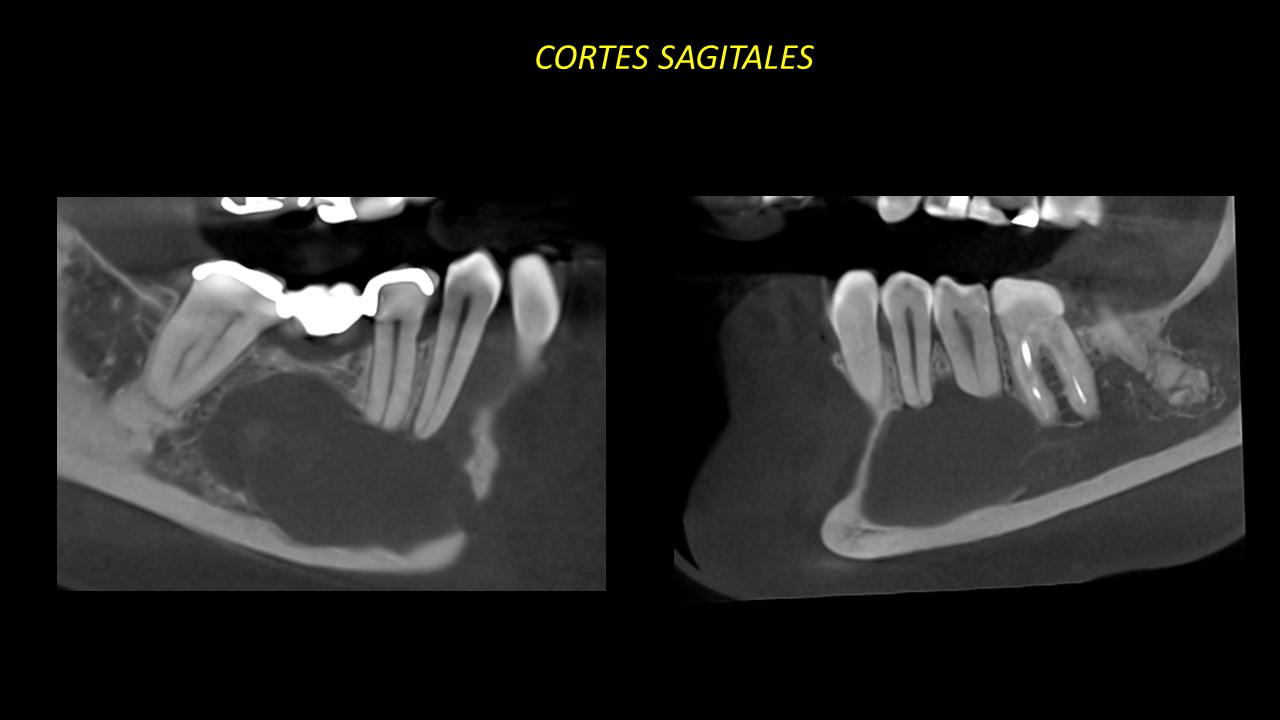

Figura 5

En los cortes coronales y sagitales podemos observar la pérdida de lámina dura a nivel apical de piezas 42,43 y 44. También se observa la reabsorción radicular externa de piezas 35,34,33,32 y 45 (Figuras 4 y 5).